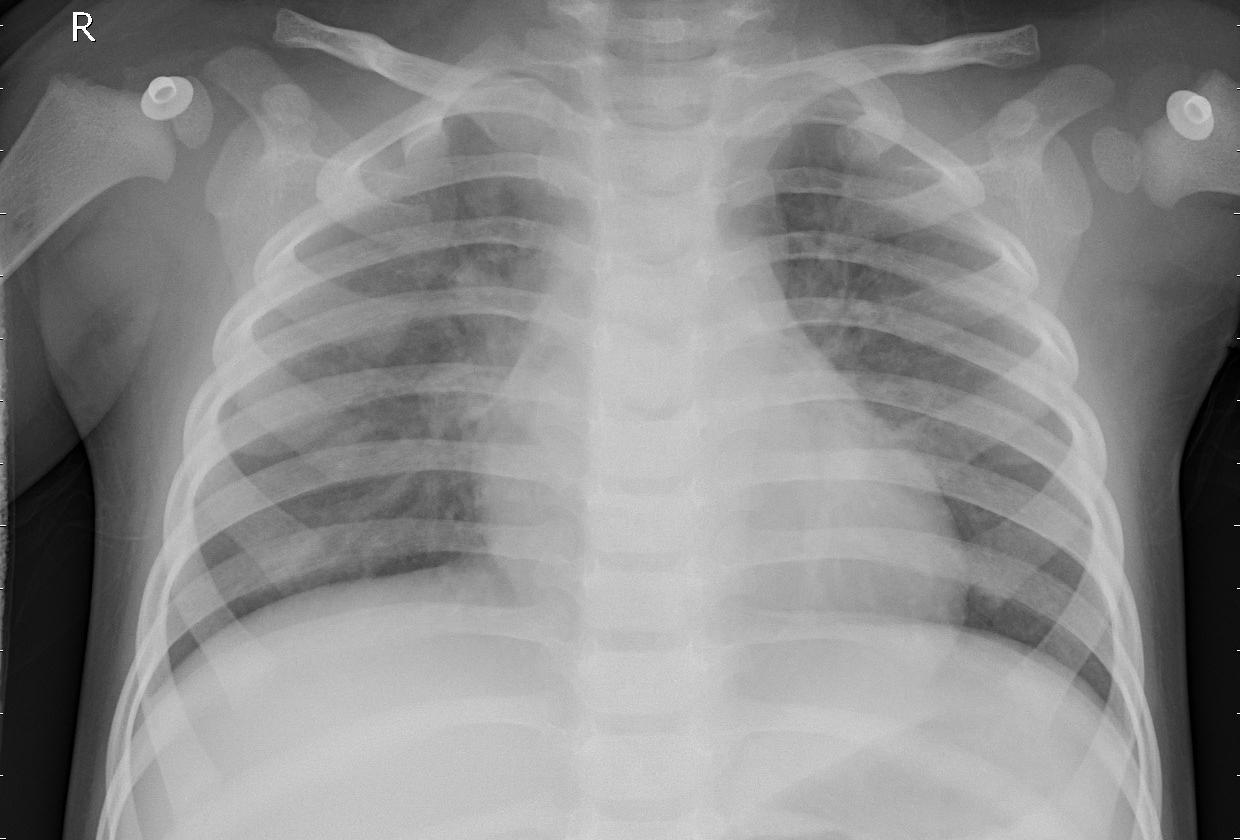

we have successful delivered AI solutions from Smart agriculture to fraud detection in banking and financial institution,medical treatment,prognosis,diagnosis and tumor detection softwares.we upgrade tradition agricultural methods to smart farming process and tools,we simplified medical access and procedures by alternating methods of diagnosis and treatment of disease with sophisticated softwares and apps

Pneumonia detection app